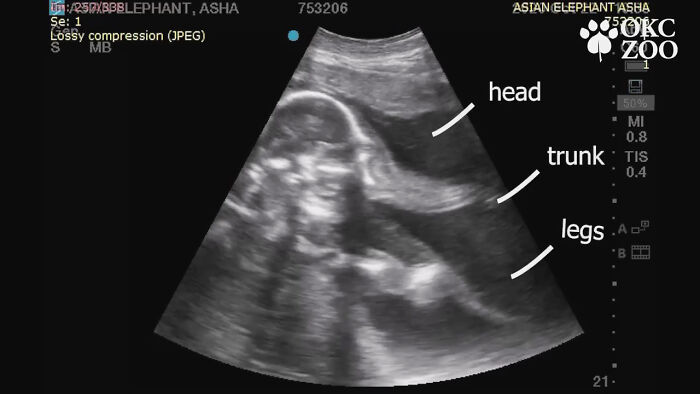

Unlike with human baby ultrasounds, which are often very hard to decipher, this one is surprisingly clear. The head, the trunk, and the legs are all vivid and easy to see, but the video also points out these parts for good measure.

In the ultrasound, one can clearly see the head, trunk and legs of the adorable baby elephant